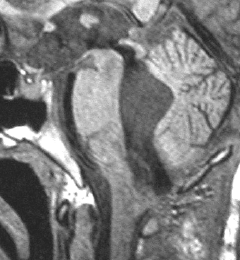

ものすごく難しい血管芽腫

これも血管芽腫です。おそらく小脳発生なのでしょうが,延髄の両側に強く癒着していて延髄の血管も腫瘍の中に入っていて,腫瘍血管には動脈瘤も合併していて破裂しました。この腫瘍を摘出するのは不可能にも思えましたが,無事にできました(下の写真)。患者さんも私もへとへとになりました。 でも,このような血管芽腫の手術はうまく行くとは限りません,手術不可能と考えた方がいいかもしれないと今でも思っています。手術すると決めればものすごく高いリスクを患者さんも外科医も背負うことになります。放射線治療をして治るサイズではないので他に治療法はありませんが (>_<) 大きな血管芽腫を手術する提案をされたら,少なくとも執刀医の経験数は尋ねましょう。